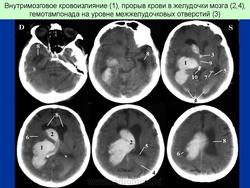

ГМ. Гематомы. Инсульт. Геморрагический и ишемический. +

Геморрагический инсульт